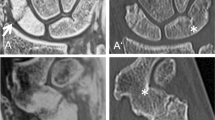

A 22-year-old male patient with acute anterior shoulder dislocation. A Sagittal intensity-inverted FRACTURE image showing the glenoid defect of the anterior margin with adjacent fracture fragments. The glenoid track in this case is 7.81 mm. B Axial FRACTURE MR image showing a small superficial Hill-Sachs lesion. The Hill-Sachs interval measured 18.1 mm. The Hill-Sachs interval is less than the glenoid track; thus, findings are characterized as on-track lesion with a low risk of engagement. C Sagittal and D axial conventional CT of the same patient showing no significant differences of the measurements of the glenoid track and Hill-Sachs index when compared to the MR-based measurements. In this case, a strong correlation between the measurements on CT and CT-like MRI was found (r = 0.93)

Intact glenoid of an 18-year-old patient with suspected traumatic shoulder injury, comparing sagittal images of an UTE, T1 GRE, and FRACTURE MR-sequence (A–C) to a conventional CT scan (D). Note the detailed bone trabecula in the gradient echo sequences T1 GRE and FRACTURE (B and C) as well as the good bone to soft tissue contrast of the UTE sequence (A) compared to CT (D). Further notice the thickening of the cortical bone in the T1 GRE and FRACTURE sequence compared to the UTE sequence (white arrows)